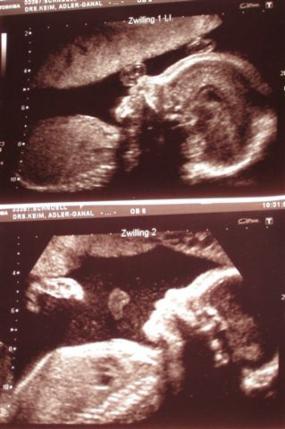

20+6, ca. 400g, oben: Jolina, unten: Tim

SSW: 24+2